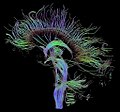

- MR – primary choice, especially axial and sagittal T1 and T2 images. In practice, DTI (diffusion tensor imaging) and FT (fiber tractography) are already commonly used for more detailed imaging of white matter pathways (their displacements, compression, etc.) due to tumor location. [5][6][7].

- Diagnostika: DTI, MRI